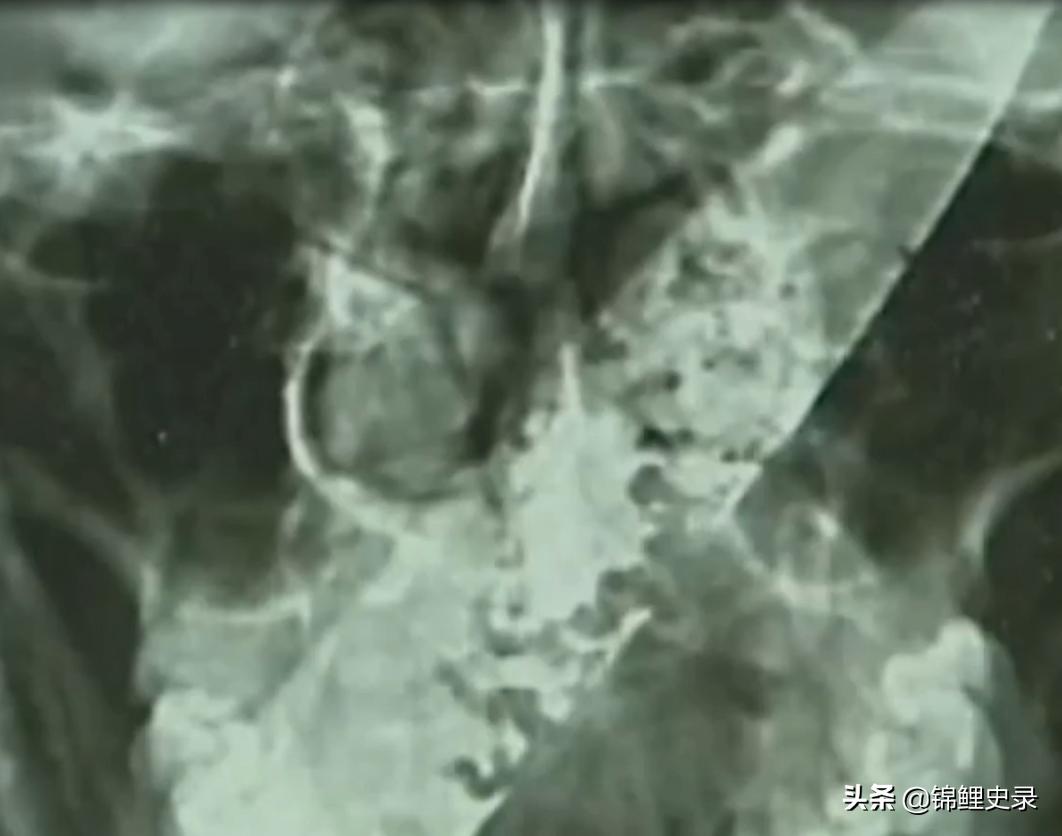

片子上显示,在福元的 头颅里 , 有一个长条状的物体 ,

从头部的右侧一直贯穿到下颌的左侧 。

这次扫描后,可以很清楚地看到,

这是一个长条形的金属物体 ,

并且从头到尾在慢慢变窄。

这竟然是一把 水果刀 。

一个人的头颅从左到右总共才不过 20厘米 ,

这把刀的长度达到了 10厘米 ,

等于横穿了半个人脑。

并且这把锋利的刀还 没有伤到大脑里的血管和神经 ,

从X光片看,这把刀确实实在福元的头颅里,

但还有一段是能够与外界接触的。

这一块已经 腐蚀 的很厉害了,

因此就产生了浓重的气味 ,